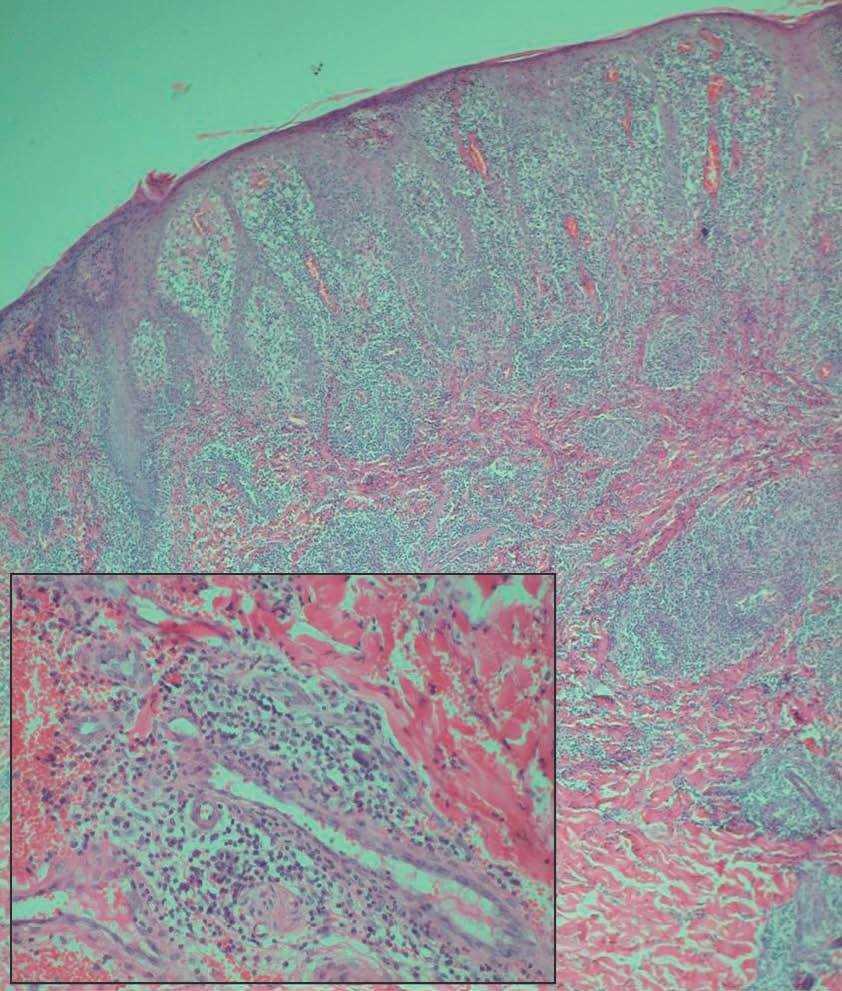

El examen histopatológico de una de las lesiones de piel de abdomen mostró la presencia de focos de necrosis epidérmica con acantosis irregular y un marcado infiltrado inflamatorio en dermis superior, distribuido principalmente en torno a los vasos dérmicos y compuesto por linfocitos y abundantes células plasmáticas (fig. 3). Los vasos dérmicos mostraban endotelios prominentes y la luz de algunos de ellos se encontraba ocluida por un material eosinófilo. No se observaron infiltrados granulomatosos ni signos de vasculitis. La técnica de Wartin-Starry no reveló la presencia de espiroquetas. El estudio inmunohistoquímico demostró que las células linfoides eran en su práctica totalidad de estirpe B.

Figura 3. Denso infiltrado inflamatorio en dermis superior, distribuido principalmente en torno a los vasos dérmicos (hematoxilina-eosina, x100) En el recuadro situado a la izquierda se observa una tumefacción del endotelio de los vasos dérmicos y un detalle del infiltrado, compuesto principalmente por linfocitos y células plasmáticas (hematoxilina-eosina, x200).

En el estudio histopatológico de las lesiones puede observarse, como en el caso que describimos, necrosis epidérmica, un denso infiltrado inflamatorio dérmico con predominio de linfocitos y células plasmáticas y afectación de vasos de calibre medio con obliteración de los mismos7,11. La detección de T. pallidum en las lesiones es variable, aunque parece que en esta forma de sífilis secundaria se observan con menor frecuencia12. En nuestro paciente no se demostraron hallazgos histopatológicos definitivos de vasculitis ni se observó la presencia de infiltrados granulomatosos.